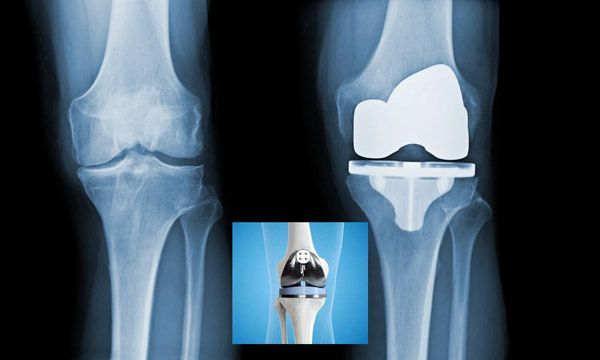

جراحی تعویض مفصل زانو یا آرتروپلاستی (Total Knee Arthroplasty)، عملی است که در آن مفصل زانوی آسیبدیده با یک مفصل مصنوعی یا پروتز از جنس موادی مانند فلز یا پلاستیک جایگزین میشود.

عکس تعویض مفصل زانو